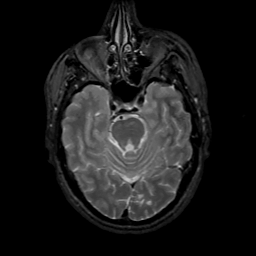

MR Study #7, March 24, 1991 -- Slice #16